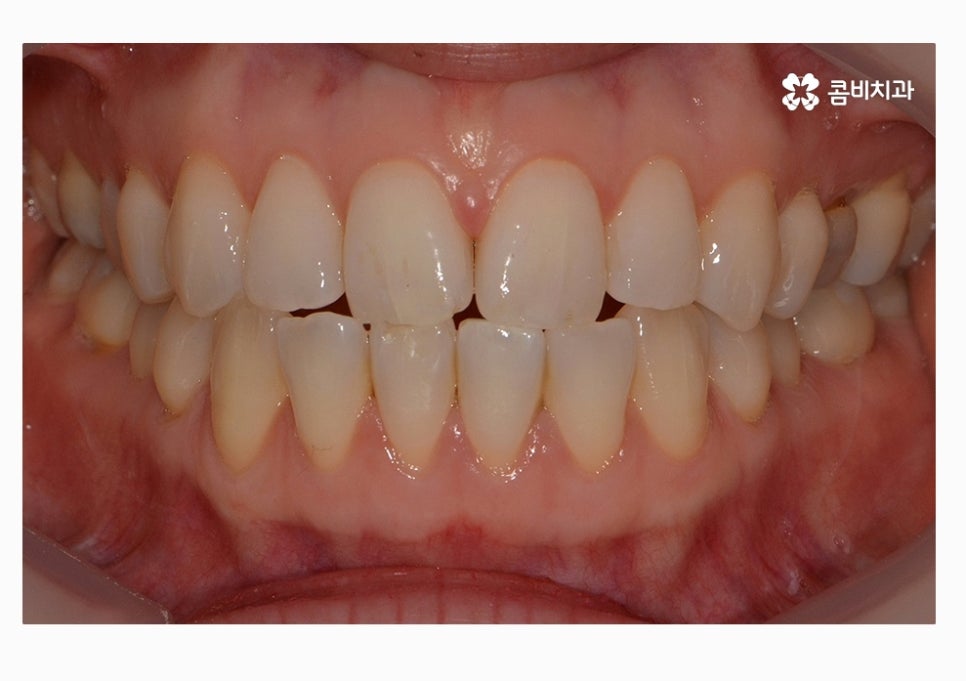

오늘 보시는 콤비교정 치료 케이스가 그러한 경우에 해당하며

정면으로 치열을 볼 때는 비교적 가지런한 편으로

보이지만 자세히 보면 부정교합에 해당한다는 것을 알 수 있어요.

치열 사진을 볼 때 정면보다는 옆모습으로 볼 때

아래 어금니가 위 어금니보다 앞으로 나와있고

앞니 교합이 제대로 맞물리지 않는다는 것이 눈에 띄게 나타나는데